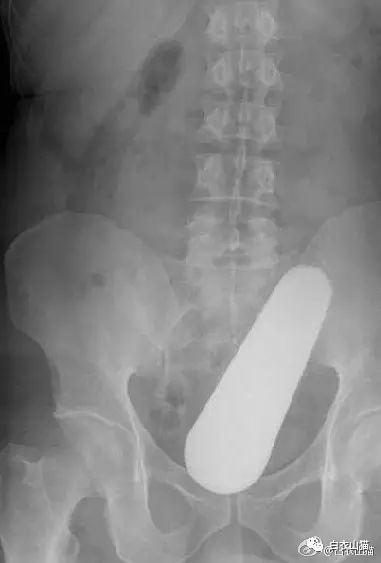

上面是前几年一名患者大肠里的黄鳝。

这条黄鳝还是雌性的黄鳝,你知道我怎么看出来的吗?

医生给他检查的时候,发现已经有腹膜炎症状,怀疑肠梗阻,拍了个片子,就是上面那个片子:一条大黄鳝在肚子里。

考虑到他已经有腹膜炎的症状,说明肠子已经有个地方破了。只能动手术了。

把肚子打开后,发现大肠破了个洞,黄鳝的头,就在那个洞里。他肚子里都是大便。他的肠子水肿很厉害。黄鳝堵住了大肠,肠梗阻,导致大肠坏死穿孔了。